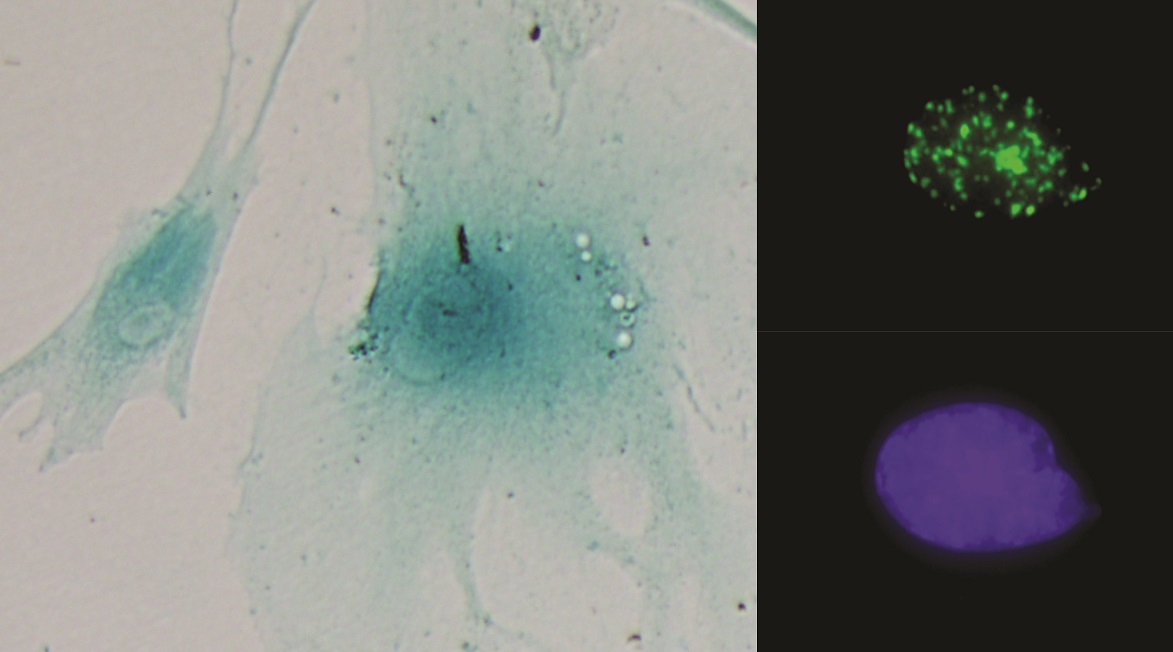

Descubren cómo llevar la inmunoterapia “a domicilio” en cáncer de mama HER2+